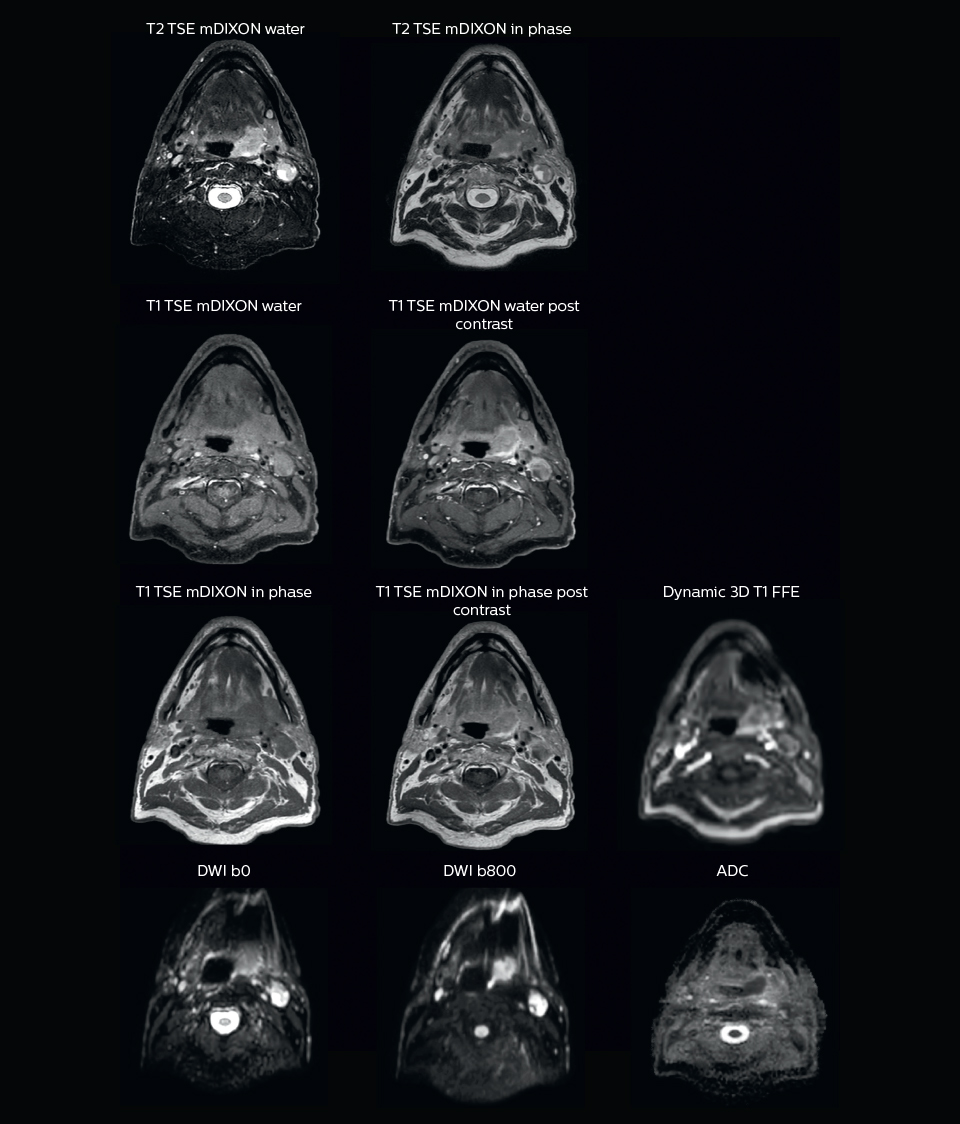

A 63-year-old patient with prostate cancer, cT3bNxM, Gleason 7, underwent MRI on Ingenia 3.0T MR-RT before radiation therapy.

Intraprostatic lesions are visible on the bTFE MR image, but not on the CT image. MRI shows excellent soft-tissue contrast for the visualization of critical structures like the rectum and penile bulb.

“We use pre- and post-contrast T1- and T2-weighted sequences with the fast and robust mDIXON method for fat suppression,” says Dr. Philippens. “Dynamic contrast-enhanced imaging is performed with high temporal resolution and low spatial resolution, to see the contrast agent uptake in the tumor. Diffusion weighted imaging is used qualitatively to see how the tumor extends into another structure, rather than for strict delineation.”